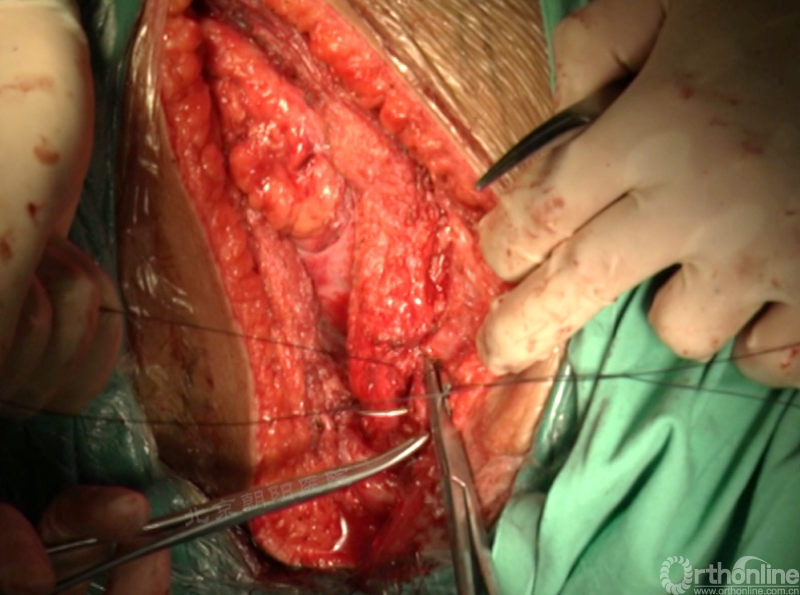

切开纤维环,去除终板椎间盘组织,直至纤维环的后侧边缘,对于严重侧凸如果需要可至后纵韧带。

进一步使用刮匙和髓核钳完整去除椎间盘组织和终板,营造植骨面。

内固定选择的是5.5mm双棒系统,先置入顶椎的螺钉垫板。

置入顶椎的椎体螺钉,螺钉可置入椎体中部到后方1/3之间的范围内。

使用双棒系统时,先置入背侧的螺钉,螺钉指向椎体中线,后置入腹侧的螺钉,螺钉轻度指向后侧。形成对椎体的三角形抓持力。

胸腔侧、腹腔侧螺钉全部置入后,骨移植物植人的越靠近后纵韧带或者纤维环的后缘越好。

椎间融合器经前方置入凹侧,确保腰椎前凸的恢复和冠状面畸形的矫正,将剩下的骨移植物置入椎间隙内。